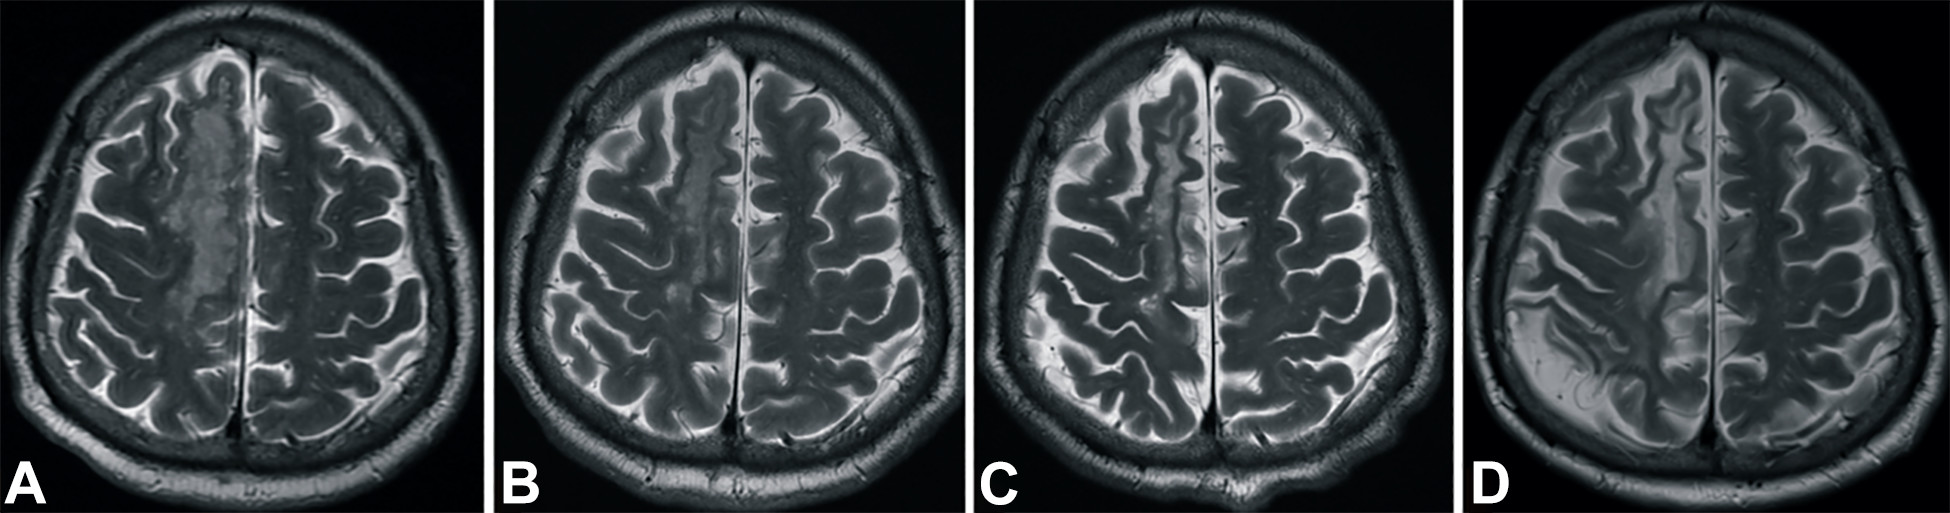

梗塞發生后2小時、8 天、3 個月和 6個月獲得的T2加權圖像顯示右側放射冠白色強度增加(圖3A-D)。